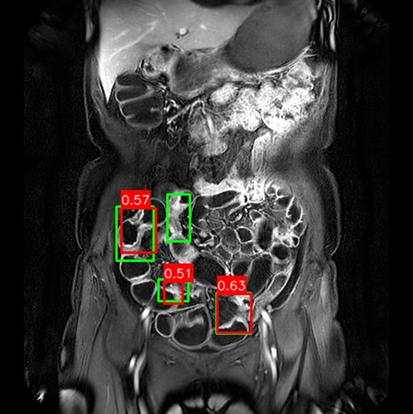

Figure 3: Qualitative Comparison on Crohn’s Disease MRE Test Set. The figure compares detection results from (a) Mask R-CNN, (b) DiffusionDet (S=3S=3), and (c) DeFloMat (Ours, S=3S=3) on challenging MRE slices. Green boxes indicate True Positives (TP, IoU 0.1\geq 0.1), Red boxes indicate False Positives (FP), and Purple boxes indicate False Negatives (FN). DeFloMat consistently demonstrates superior localization quality and sensitivity: it successfully detects subtle inflammation regions (TP) that are often missed (FN, Purple boxes) by the Mask R-CNN baseline (Row 2, 4). Furthermore, DeFloMat provides tighter bounding box localization compared to DiffusionDet, confirming the benefit of learning the direct, deterministic flow field. The results show DeFloMat’s robustness in capturing varying sizes and numbers of inflammatory lesions.